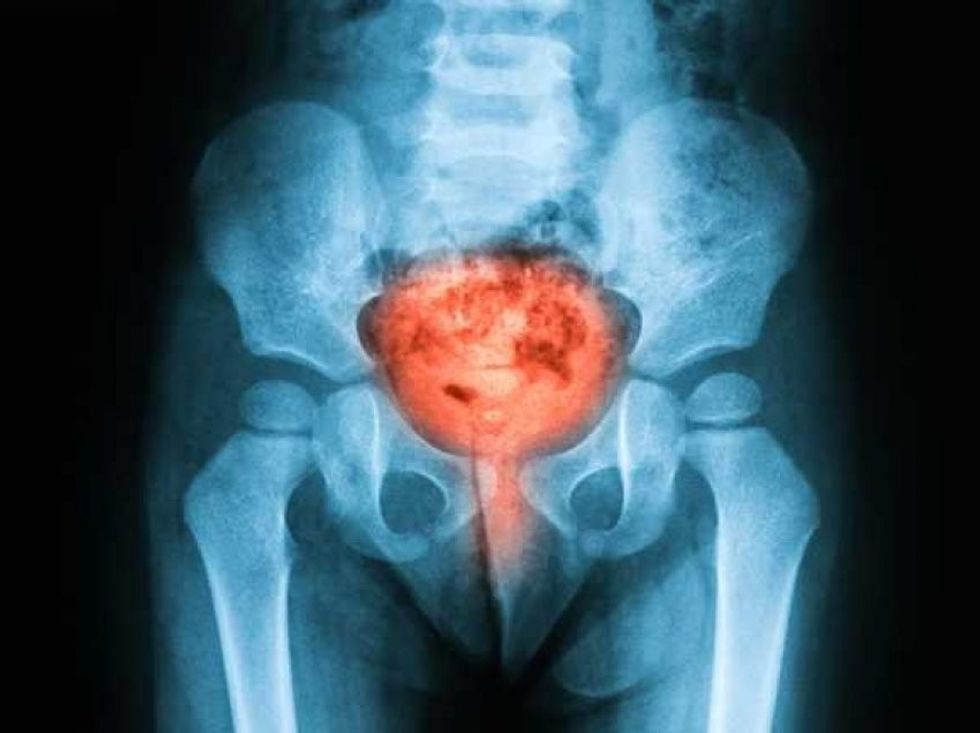

Kanceri i prostatës është rezultat i shumëzimit të qelizave kancerogjene në mënyrë të pakontrolluar në prostatë - një gjëndër e vogël në formë arre te burrat

Probleme të tjera të urinimit që mund të sinjalizojnë kancerin e prostatës përfshijnë: tendosje ose vështirësi në fillimin e urinimit, një rrjedhje e dobët e urinës, ndjenja se nuk jeni në gjendje ta zbrazni plotësisht fshikëzën tuaj, prania e gjakut në urinë.